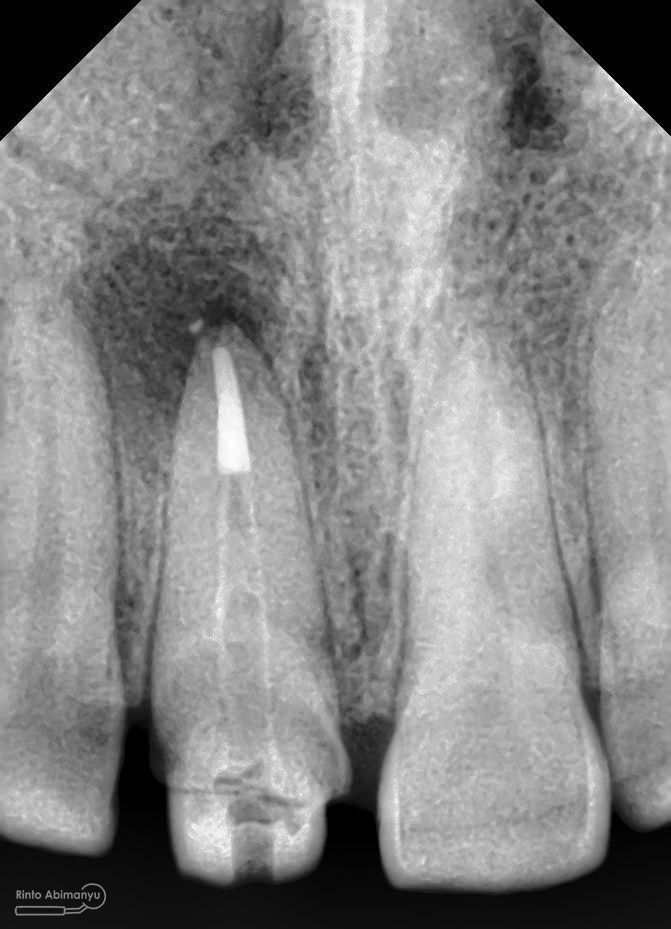

dan ini foto ronsen nya…

Foto radiografis gigi 11 21 22 yang mengalami fraktur

Dari pemeriksaan radiografis lokasi fraktur menyerempet kamar pulpa pada ketiga gigi tersebut… Saya sampaikan kepada pasien bahwa ketiga gigi tersebut memerlukan perawatan saluran akar terlebih dahulu baru kemudian dilanjutkan dengan restorasi indirek… kenapa saya pilih restorasi indirek? Pertimbangannya adalah sisa struktur mahkota gigi yang ada bila hanya di “sambung” dengan restorasi direk dalam jangka panjang rentan mengalami kerusakan, yang kedua pemilihan warna akan lebih maksimal pada kasus ini…. Pasien setuju dengan rencan perawatan yang saya jelaskan…

Oo iya tidak lupa juga dilakukan foto ronsen setelah pemasangan crown…

Foto radiografis akhir

Dari foto ronsen terlihat gambaran yang “indah” dari mulai pengisian saluran akar yang rapat dan padat serta gambaran sementasi mahkota yang terlihat homogen….